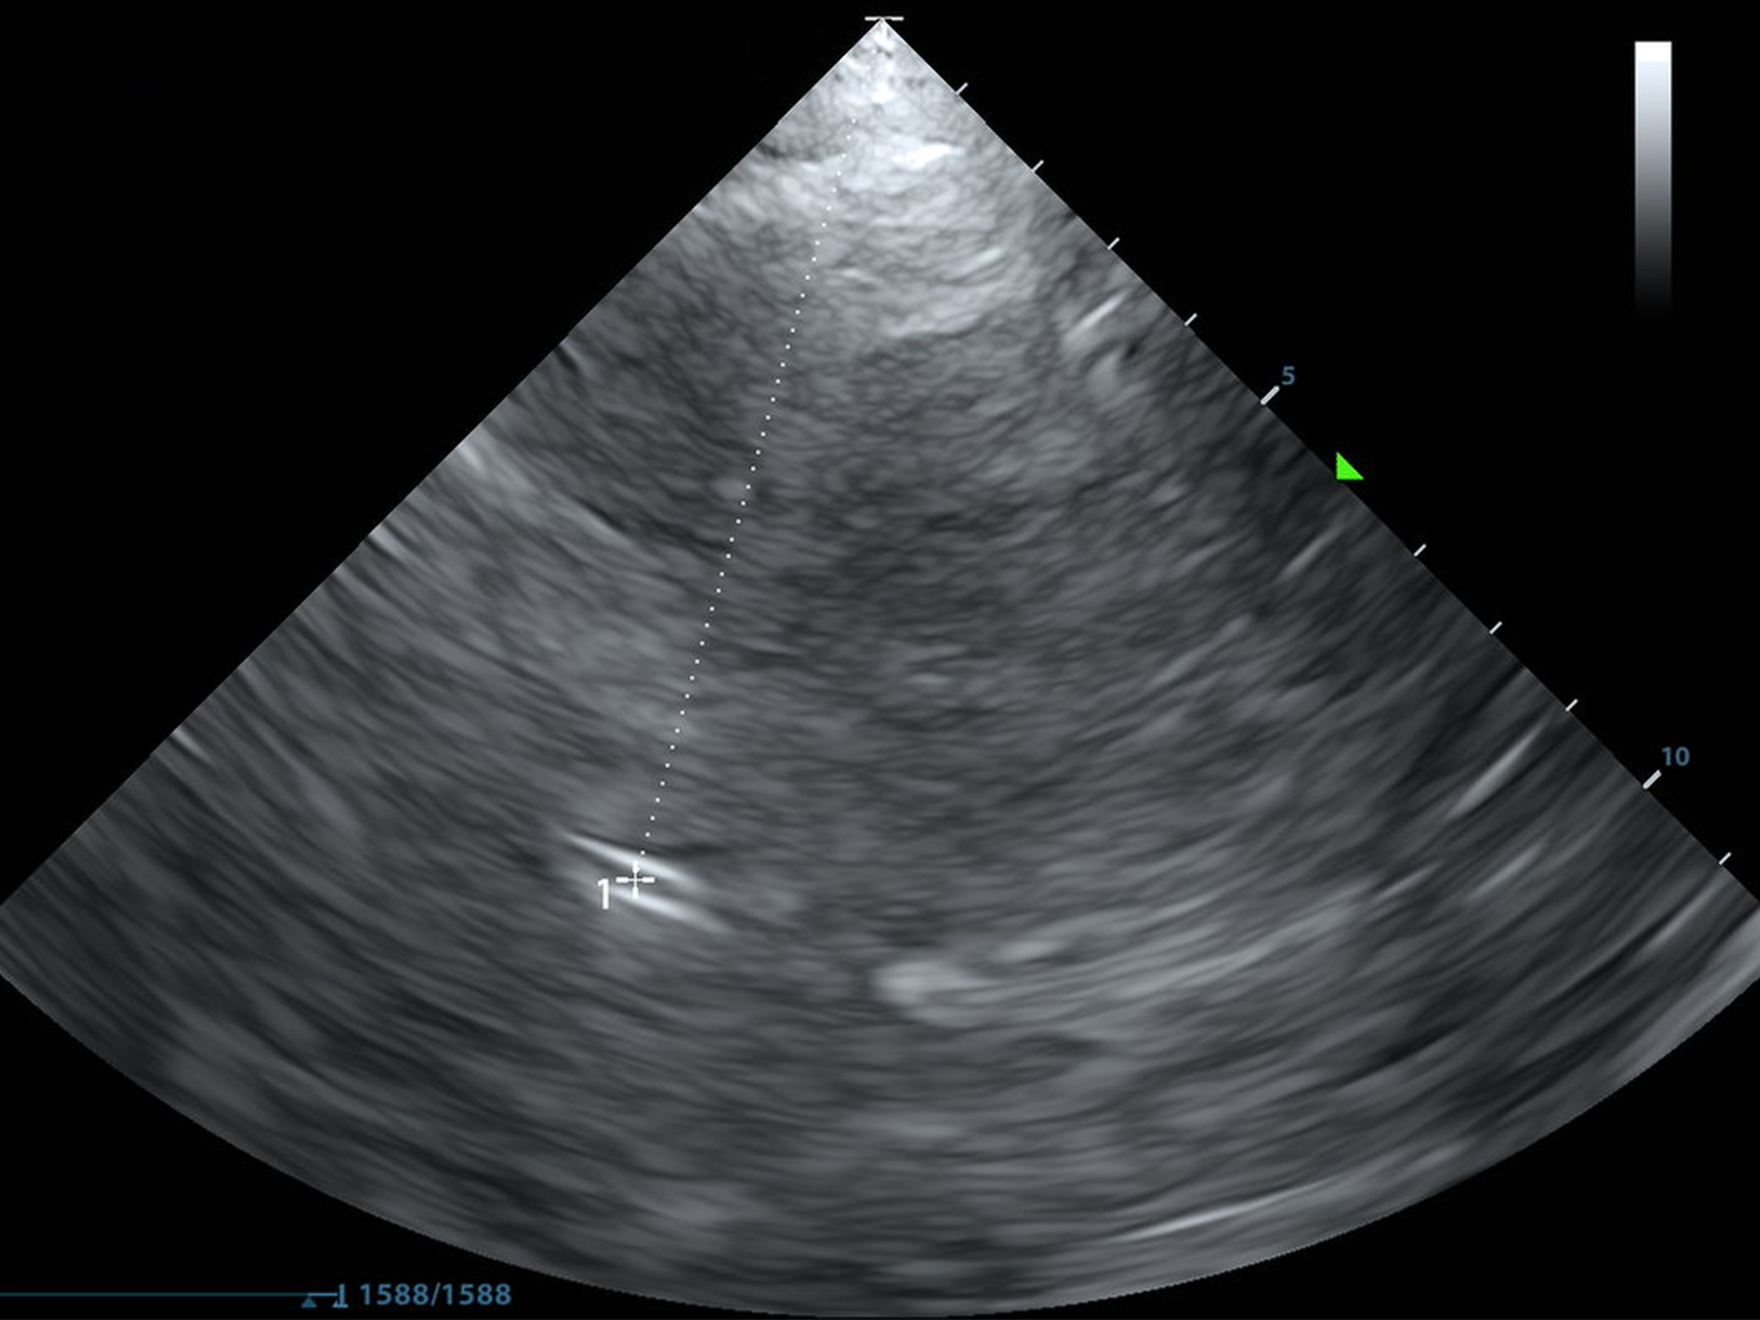

The Basics

B-Mode Anatomy